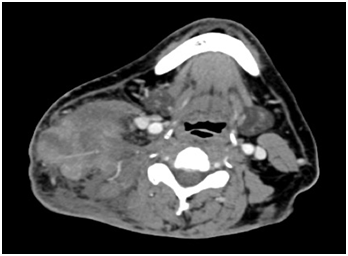

We are presenting a clinical case from our files, with an authorized informed consent assessed by the ethical and academic committee of the institution, a 34-year-old male identified as Mexican mestizo, with large exophytic lesion in the posterior triangle of the neck, without significant history. Physical exam: Tumor 10x10cm, exophytic, sessile base, associated with multiple metastases in bilateral neck lymph levels II- V right tumor burden greater than 10cm (Figure 1) (Figure 2). The histopathological report (HPR): poorly differentiated adenocarcinoma mucoproductor. PET/CT reports tumor metabolic activity in posterior triangle of the neck injury dependent and bilateral regional lymph node involvement with subcutaneous cellular tissue.

Figure 2 CT Scan, Tumor> 10cm in the posterior cervical region, with affection of subcutaneous tissue.